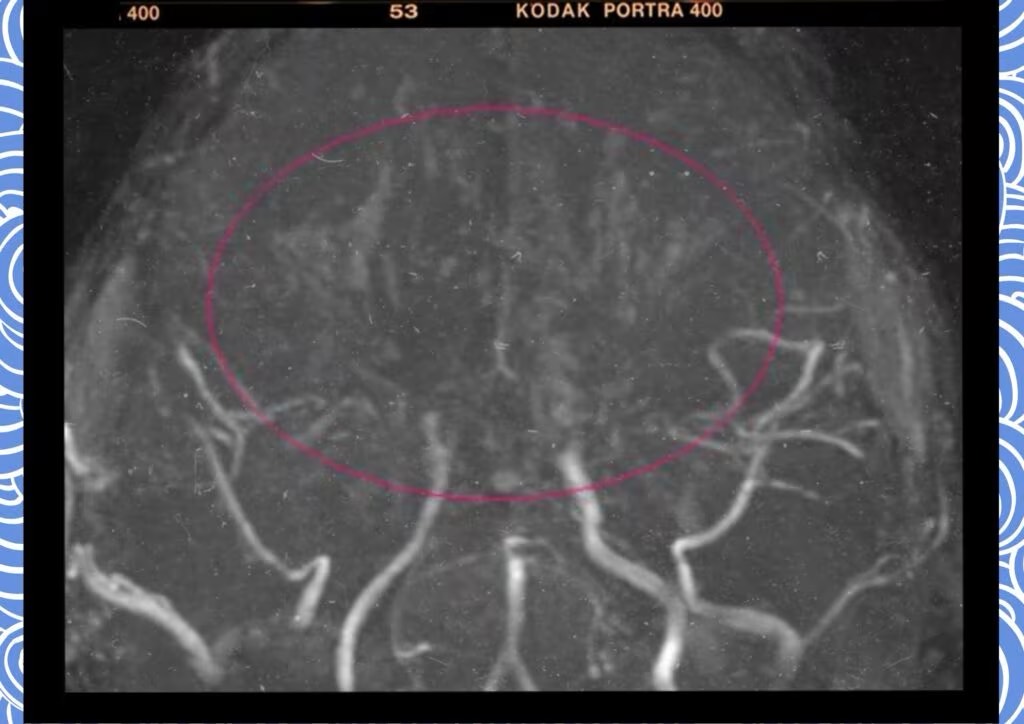

모야모야병은 뇌혈관, 특히 뇌로 혈액을 공급하는 내경동맥과 그 주변 주요 혈관이 점점 좁아지고 막히는 희귀 난치성 질환으로, 혈류가 줄어든 뇌는 부족한 혈액을 보충하기 위해 가느다란 미세측부혈관들을 새로 만들어냅니다. 이 작은 혈관들이 연기처럼 보인다고 하여 일본어로 ‘모야모야(안개·연기)’라는 이름이 붙었습니다. 소아부터 성인까지 폭넓게 나타나며, 특히 5~10세 어린이와 30대 전후의 여성에서 비교적 많이 발견되는 경향이 있습니다. 증상은 일시적 마비, 언어장애, 두통, 실신, 경련 등 매우 다양해 뇌졸중과 유사하거나 초기에는 가벼운 신경학적 증상으로만 나타나 진단이 늦어지기도 했습니다. 질환이 진행하면 허혈성 뇌졸중(뇌경색)이나 출혈성 뇌졸중 위험이 증가하여 반드시 전문적인 관리가 필요합니다. 아직 완전히 예방할 수 있는 방법은 없지만 조기 진단과 적절한 치료를 통해 뇌 기능을 보호하고 삶의 질을 유지할 수 있습니다.

모야모야병은 뇌기저부의 주요 혈관이 서서히 협착되고 막히면서 뇌혈류가 감소하는 만성 진행성 뇌혈관 질환입니다. 협착이 진행된 부위를 대신해 뇌는 생존을 위해 얇고 약한 혈관망을 만들어 혈류를 보충하려 하고, 이 새로운 혈관들이 촬영 영상에서 연기처럼 퍼져 보인다고 하여 ‘모야모야’라는 이름이 붙었습니다. 기전적으로는 내경동맥 말단부와 중대뇌동맥·전대뇌동맥의 기시부에 병변이 가장 잘 생기며, 시간이 지남에 따라 양쪽에 대칭적으로 나타나는 특징을 보였습니다. 이 질환은 단순한 혈관 협착이 아니라 진행성 변화이기 때문에 치료하지 않으면 혈류 부족이 심해지고 뇌 손상이 누적될 수 있습니다. 또한 뇌기능이 체력·호흡·체온 변화 등에 민감하게 반응하기 때문에 과호흡, 울음, 격렬한 운동, 감염 등으로 증상이 악화될 수 있습니다. 즉, 모야모야병은 시간이 지나면서 뇌혈류를 감소시키고 뇌졸중 위험을 높이는 질환이며, 평생 관리가 필요한 만성적 특성을 갖고 있습니다.

따라서 가족력이 있거나 의심되는 증상이 있다면 뇌 MRA·MRI 등의 정기검진이 도움이 되며, 조기 진단 시 치료 효과도 훨씬 높아집니다.